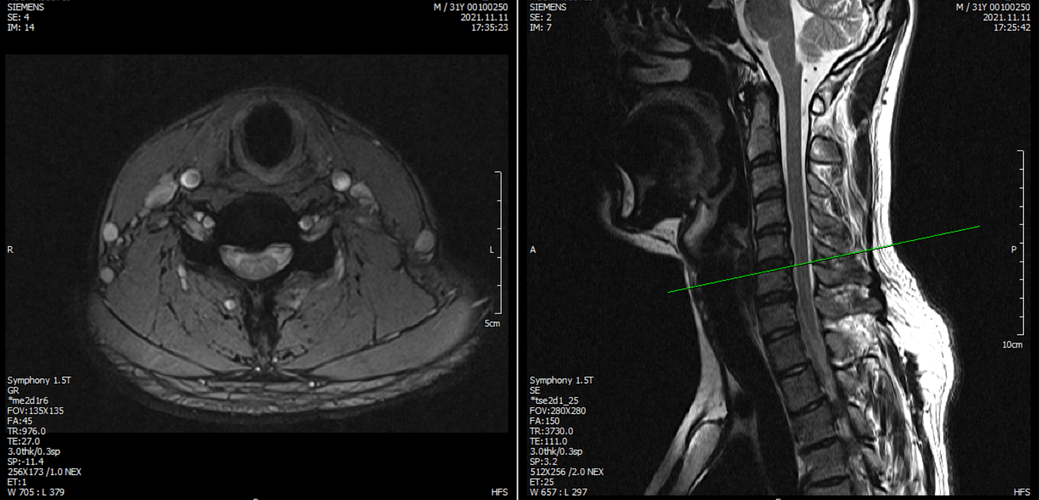

※우리들병원 (신경외과 대표원장) : 경추,요추 MRI 촬영했고 요추는 매우 건강하고 경추에는 일자목에 퇴행성 디스크가 보이지만 한쪽팔에 저림이나 힘빠짐을 유발할 정도는 절대아니고, 다른 원인을 찾아야한다고 했습니다.

※동네 신경외과 : 앞서 모든 설명은 잘못된것, 디스크가 나이에 비해 매우 심하고 일자목이 아닌 역C자목임, 경추에 디스크가 찢어진 것이 보이는데 이런 구조적 변화가 화학적반응을 일으켜 신경을 자극할 수 있음. 약을 먹어야하고 안되면 주사치료해야함, 300만원짜리 교정치료도 해야함.

3명이 디스크가 아니라고 하는데 1명이 디스크일수 있다고 하니까 조금 어렵습니다. 경추디스크가 약간은 있으니 팔저림은 설명할수 있다해도 다리저림은 설명이 안됩니다.. MRI 결과상 요추는 매우 건강하다고 하셨거든요.

아래는 저의 경추과 요추 MRI 사진 첨부합니다.